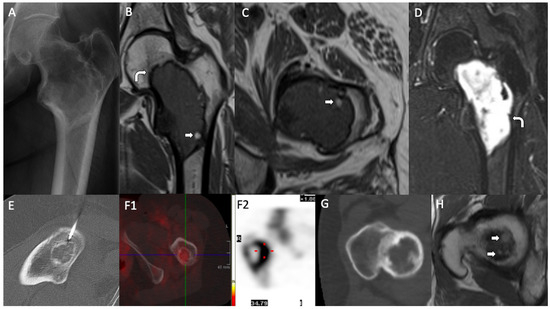

| 1 | M, 26 | R | Femur | P | IT | Pathological fracture | Ly, Sc rim | INA | 95% Fibromixoid | Stellated, spindled No atipia | 3% Psamomatoid | No | No | 2% | No | Small, hyalinized | No | No | - | No | Not performed | Curettage and bone grafting | 312 months, NED |

| 2 | F, 24 | R | Femur | P | IT | ID | INA | INA | 75% Fibromixoid | Stellated, spindled No atipia | 4% Psamomatoid | 15% Peripheral | 1% | 5% | No | Small, hyalinized | Mast cells | No | - | No | Not performed | Curettage and bone grafting | 215 months, NED |

| 3 | M, 61 | R | Femur | P | IT | ID (Hodgkin lymphoma extension study) | INA | INA | 20% Fibromixoid | Stellated, spindled No atipia | 40% Gross trabeculae, Pagatoid | 40% Intermixed | No | No | No | Small, hyalinized | Mast cells, lymphocytes | No | - | No | Not performed | Curettage and bone grafting | 192 months, NED Death (multi-organ failure) |

| 4 | M, 19 | L | Femur | D | - | Pain | Ly, cystic, internal trabeculae | Ly, cystic, internal trabeculae T2WI: HI Fat areas | 80% Hyalinized | Stellated, spindled No atipia | 3% Psamomatoid | 10% Intermixed | 6% | No | 1% | Small, hyalinized | No | No | - | No | Not performed | Curettage and bone grafting, nail-plate | 281 months, NED |

| 5 | M, 28 | L | Femur | P | IT | ID | Ly, Sc rim | Ly, Sc rim T1WI: isointense T2WI: HI | 95% Fibromixoid | Stellated, spindled No atipia | 2% Trabeculae | No | 3% | No | No | Small, hyalinized | Mast cells | No | - | No | Not performed | Curettage and bone grafting, nail-plate | 145 months, NED |

| 6 External case | F, 48 | R | Femur | P | IT | Pain | Ly, cystic, internal trabeculae | INA | 75% Fibromixoid | Stellated, spindled No atipia | 10% Trabeculae | 2% Intermixed | No | No | 3% | Small, hyalinized | No | 10% Ischemic | ABC –like areas | No | Not performed | Curettage and bone grafting | 303 months, NED |

| 7 | F, 20 | L | Femur | P | IT | Pain Previous local trauma | INA | INA | 95% Fibrous | Stellated, spindled No atipia | 2% Psamomatoid | No | 1% | 3% | No | Small, hyalinized | No | No | - | No | Not performed | Curettage and bone grafting, nail-plate | 134 months, NED |

| 8 | M, 68 | R | Femur | P | IT | ID | Ly, Sc rim | Sc rim, internal septae PET: no uptake | 70% Fibromixoid | Stellated, spindled No atipia | 30% * Trabeculae * CNB | No | No | No | No | Not seen | Plasma cells | No | - | No | Not performed | Curettage and bone grafting | 167 months, NED |

| 9 | M, 19 | R | Femur | P | IT | Pain | WD, Ly, Sc rim | Bone scintigraphy and PET: peripheral uptake | 77% Mixoid > fibro | Stellated, spindled No atipia | 3% Trabeculae | No | No | 15% | 5% | Small, hyalinized | Lymphocytes, hemosiderophages | 1% Ischemic | - | No | NGS: TP53 mutation (c.520A > T, p.Arg174Trp) | Curettage and bone grafting, nail plate | 38 months, NED |

| 10 | F, 50 | L | Femur | P | IT | ID (ovarian tumor extension study) | WD, Ly, Sc rim | T1WI: hi T2WI: HI SPECT: moderate homogeneous uptake | 50% Fibromixoid | Stellated, spindled No atipia | 50% * Trabeculae * CNB | No | No | No | No | Not seen | No | No | - | No | Not performed | Expectant management | 13 months, NED Death (ovarian tumor) |

| 11 | F, 52 | L | Femur | P | IT | Pain | WD, Ly, Sc rim | T1–WI: hi T2–WI: HI Fat areas | 90% Fibromixoid, dense collagen bands | Stellated, spindled No atipia | 5% Psamomatoid | No | 2% | No | 3% | Small, hyalinized | Lymphocytes | No | - | No | NGS: GNAS mutation (c.2530C > T, p.Arg844Cys ) | Curettage and bone grafting | 41 months, NED |

| 12 External case | F, 72 | L | Femur | P | IT | Pain | WD, Ly, Sc rim | INA | 94% Fibromyxoid | Stellated, spindled No atipia | 5% Psamomatoid | No | No | 1% | No | Not seen | No | No | - | No | Not performed | Curettage and bone grafting | 240 months, NED Natural death |

| 13 | M, 38 | R | Femur | P | IT | Pathological fracture | INA | T1WI: hi T2WI: HI Fat areas | 25% Fibromyxoid | Stellated, spindled No atipia | 30% Pagetoid | 10% Intermixed | 5% | No | No | Small, hyalinized | No | No | Bone infarct (30%) | No | Not performed | Curettage and bone grafting | 257 months, NED |

| 14 External case | F, 26 | L | Femur | P | IT | ID | INA | INA | 72% Fibromyxoid | Stellated, spindled No atipia | 15% Ttrabeculae, pagatoid, psamomatoid | 1% Intermixed | 4% | 8% | No | Small, hyalinized | Perivascular plasma cells and lymphocytes | No | - | No | Not performed | Curettage and bone grafting, nail plate | 129 months, NED |

| 15 | M, 18 | R | Femur | P | IT | Pain | INA | INA | 60% Mixoid > fibro | Stellated, spindled No atipia | 30% Trabeculae | 10% Intermixed | No | No | No | Big, hyalinized | Hemosiderophages | No | - | No | Not performed | Curettage and bone grafting | 131 months, NED |